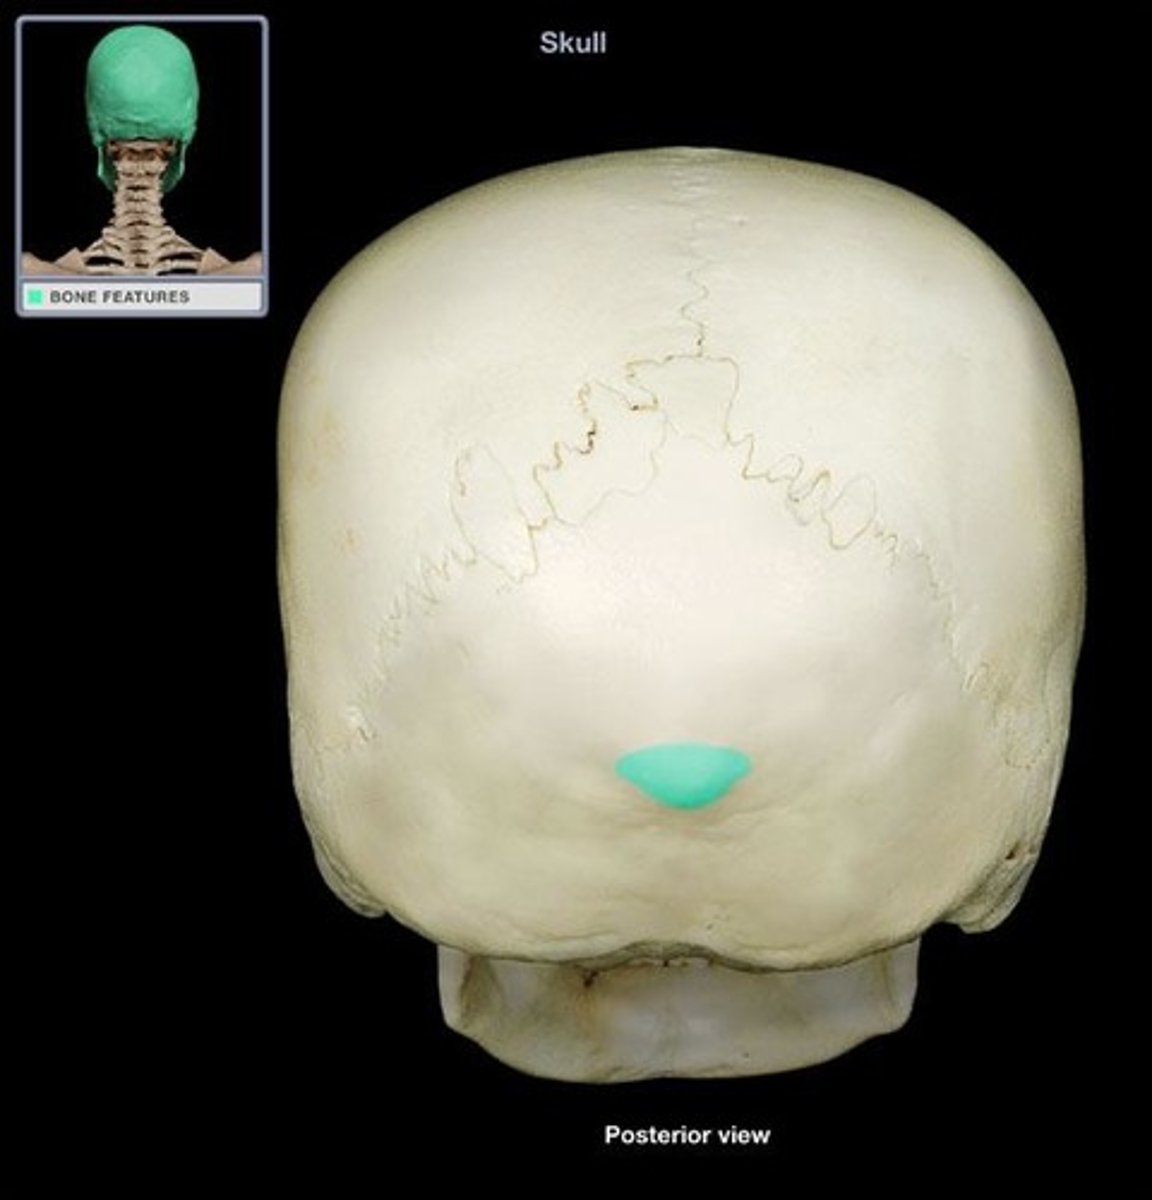

external occipital protuberance